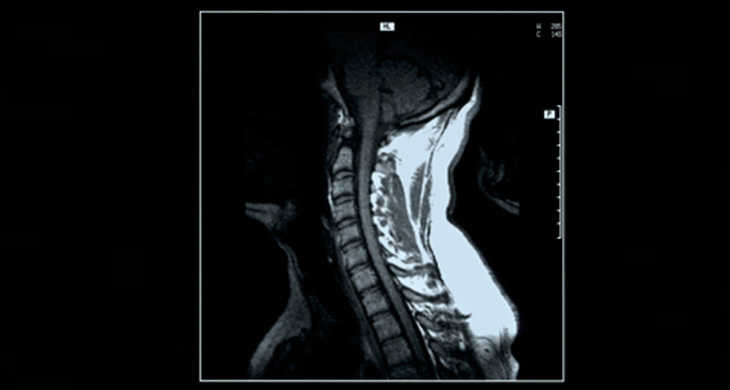

【参考】